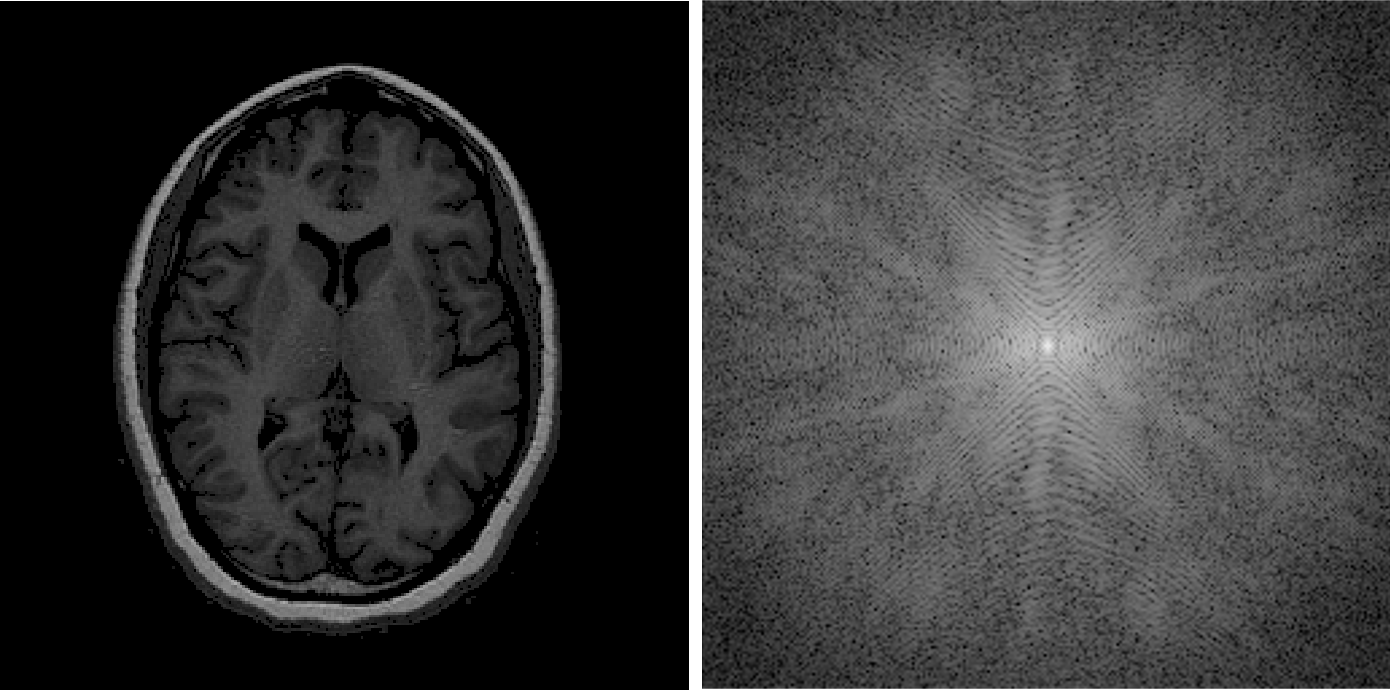

K空间特点:

(1)填入k空间不同位置的数据大小不同,中心信号强,空间频率低;外围信号弱,频率高。

(2)储存在k空间不同位置的MR信号对图像的贡献不同

填充在k空间的中心区域的MR信号幅度大,主要决定图像的对比;填充在k空间周边区域的MR信号幅度小,主要决定图像的空间分辨力。

(3)k空间的对称性

具有空间共轭对称性,可用来实现快速成像。

k空间在相位编码方向上和频率编码方向上都是镜像对称的。

(4) k空间与成像物理空间

k空的每一个一个数据点都是断层上所有体素的贡献,虽然二维空间是由二维数据点构成,但并不与物理空间直接对应